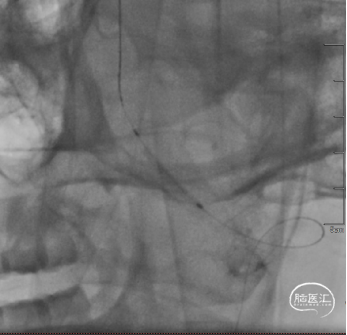

双导丝“悬吊技术”稳定指引导管。

Ultra-soft球囊(3*20mm)扩张椎动脉开口。

球囊扩张术后复查示左侧椎动脉开口狭窄改善。

造影进一步证实左侧椎动脉V4段重度狭窄,狭窄远端小脑后下动脉发出,基底动脉中段中度狭窄。

使用双导丝及球囊辅助导管通过技术,将6F指引导管送至V2段。

Ultra-soft球囊(2*20mm)扩张椎动脉V4段。

球囊扩张椎动脉V4段狭窄改善。

V4段支架置入术后,PICA保留。

Maurora® 4mm*16mm雷帕霉素药物洗脱支架定位。

球扩释放Maurora® 4mm*16mm雷帕霉素药物洗脱支架。

术后即刻复查示开口狭窄明显改善。

术后复查支架成形满意,前向血流3级。